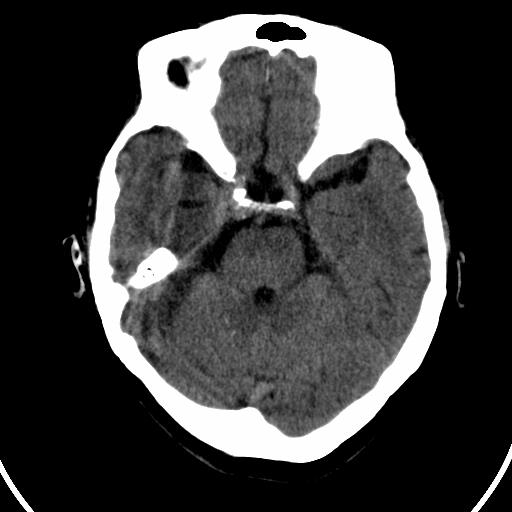

今天碰到的病人,发图上来,大家帮看看该如何诊断?

双侧小脑齿状核钙化,患者是成年人就无病理意义。

双侧小脑齿状核钙化

双侧小脑齿状核钙化,生理性钙化

考虑甲状旁腺功能低下

双侧小脑齿状核钙化 ,原因挺多,有生理性也有病理性的